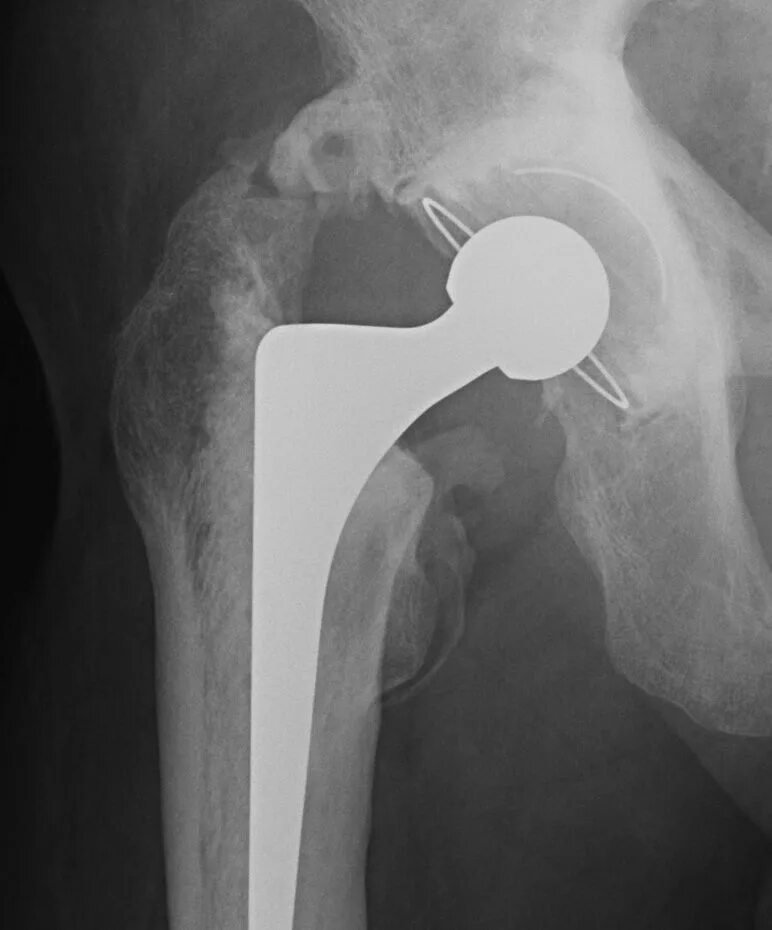

Бесплатное эндопротезирование тазобедренного сустава